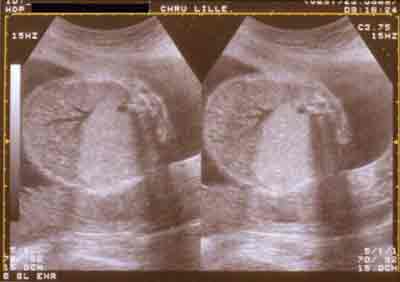

Diagnostic différentiel (hernie droite) : MAKP type III Stocker